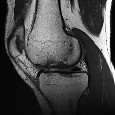

Question 8:

A 30-year-old man falls from a height and sustains a talar neck fracture. Six weeks postoperatively, an AP radiograph of the ankle reveals a subchondral radiolucent band extending across the dome of the talus. What is the clinical significance of this radiographic finding?

Correct Answer: It suggests intact vascularity to the talar body.

Explanation:

The finding described is Hawkins sign, which is a subchondral radiolucent band seen in the talar dome 6 to 8 weeks after a talar neck fracture. It represents subchondral osteopenia secondary to hyperemia from disuse. Its presence is a positive prognostic indicator, confirming that the talar body has an intact blood supply and is unlikely to develop avascular necrosis.